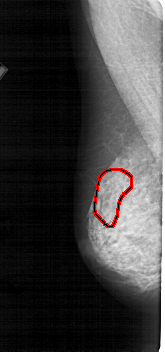

A_1145_1.LEFT_MLO

FILE: A_1145_1.LEFT_MLO.OVERLAY

TOTAL_ABNORMALITIES 1

ABNORMALITY 1

LESION_TYPE CALCIFICATION TYPE PLEOMORPHIC DISTRIBUTION SEGMENTAL

ASSESSMENT 4

SUBTLETY 3

PATHOLOGY MALIGNANT

TOTAL_OUTLINES 1

BOUNDARY